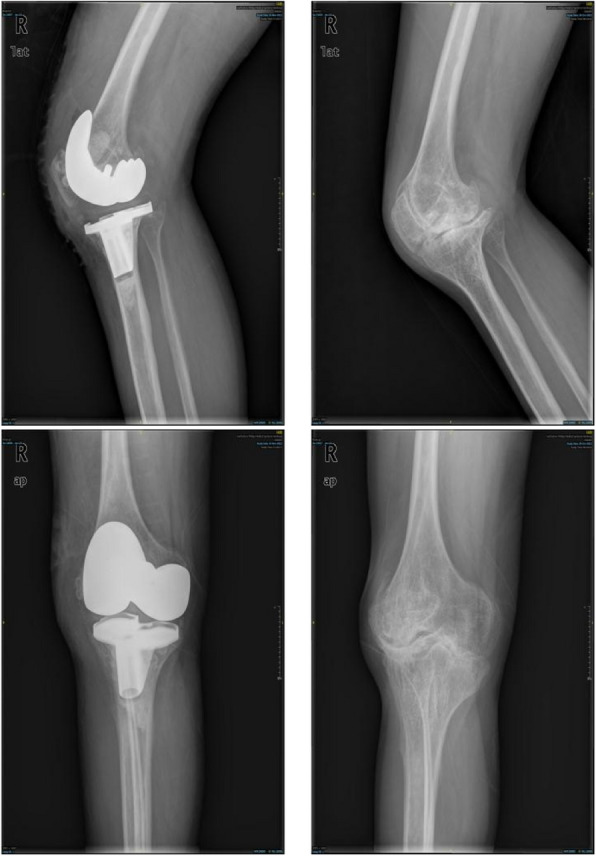

Methods: Between January 2008 and December 2021, 22 male patients with ankylosed knees in the extended position due to hemophilia underwent TKA. The average age of the patients was 41.3 years (range, 19 to 52 years), and the average hospital stay was 33.4 days (range, 14 to 50 days). TKA was performed using quadriceps tendon Z-lengthening plasty, staged osteotomy, and comprehensive soft-tissue release. A variety of methods were used to evaluate the postoperative clinical outcomes and complications, including range of motion (ROM) assessment, Visual Analogue Scale (VAS), Knee Society Score (KSS), and the Western Ontario and McMaster Universities Osteoarthritis Index (WOMAC).

Results: At the last follow-up, the average KSS increased from 75.14 ± 34.63 before surgery to 148.41 ± 27.74 (P < 0.001), the ROM increased from 0 to 86.14 ± 24.69 (P < 0.001), the WOMAC score changed from 28.05 ± 11.20 before surgery to 10.82 ± 11.00 (P < 0.001), and the average VAS score decreased from 2.86 ± 1.86 to 0.73 ± 1.20 (P < 0.001).

Conclusion: Although the recovery of range of motion is lower than normal and there is a relatively high incidence of complications, TKA can still significantly improve the flexion and extension functions, mobility, and quality of life of patients with ankylosed knees.